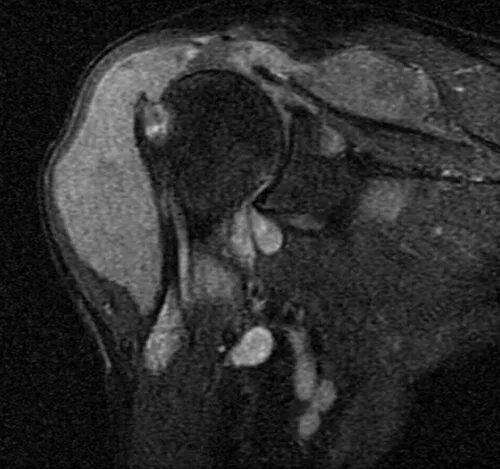

Пигментный виллонодулярный синовит